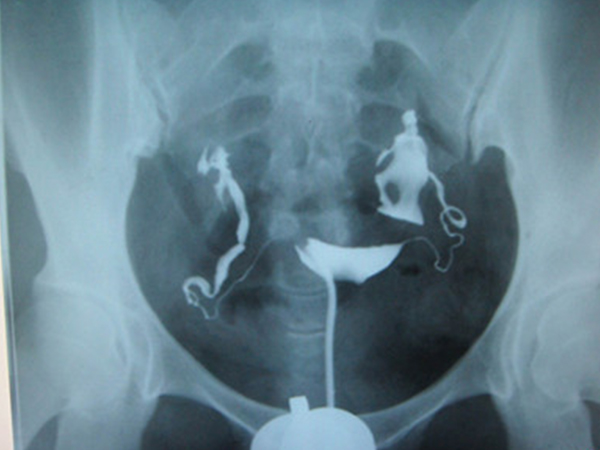

输卵管造影技术需要通过导管向宫腔注入造影剂,并通过X射线拍摄影片,然后医生会根据拍摄到的输卵管的情况去判断患者是否存在输卵管的问题。该技术不仅能够直观的展示输卵管的形态以及是否通畅,还能够明确阻塞的部位、有无畸形、有无粘连或者病变的,通过这项检查能够排除不孕患者输卵管的不孕因素。

由上述可知输卵管造影是需要通过导管向检查部分输送造影剂的,如果输卵管正常,那么就能看到一侧或两侧的输卵管伞端有造影剂溢出,且盆腔也有造影剂的涂抹的痕迹。

2、输卵管造影显示堵塞

输卵管造影片子中能看到一侧或者两侧输卵管不显影或者是部分显影,且盆腔没有造影剂涂抹的痕迹。如果出现上述情况,但是盆腔有造影剂涂抹痕迹,则证明输卵管一侧是通畅的。

3、输卵管造影显示积水

如果做完输卵管造影后,拿到的片子显示一侧或者两侧的输卵管远端增大、膨胀,则存在输卵管积水的问题。